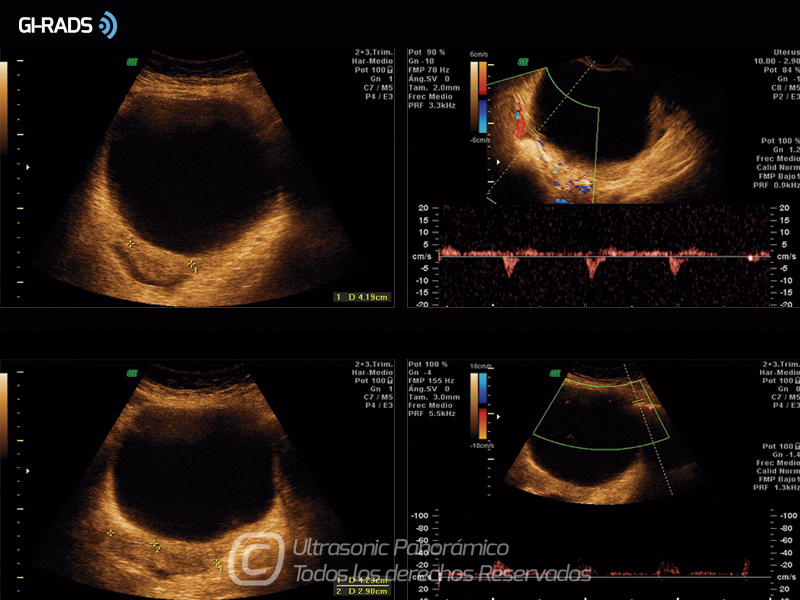

• Patologías Benignas – Cistoadenoma